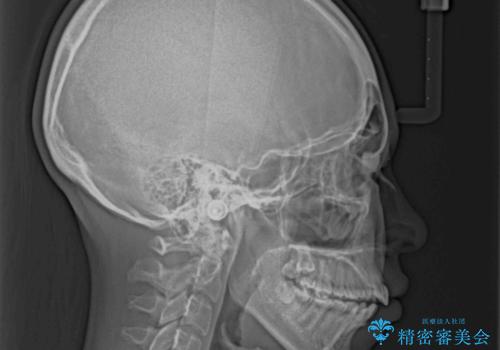

舌の突出癖により上下の前歯は非接触であり、更には奥歯の咬み合わせが非対称となっている状態でした。

通常は上下左右の第一小臼歯4本を抜歯することになりますが、右側臼歯部の咬合が上顎前突気味であったため、下顎右側のみ第二小臼歯を抜歯し、ワイヤー装置にて矯正治療を行うこととしました。